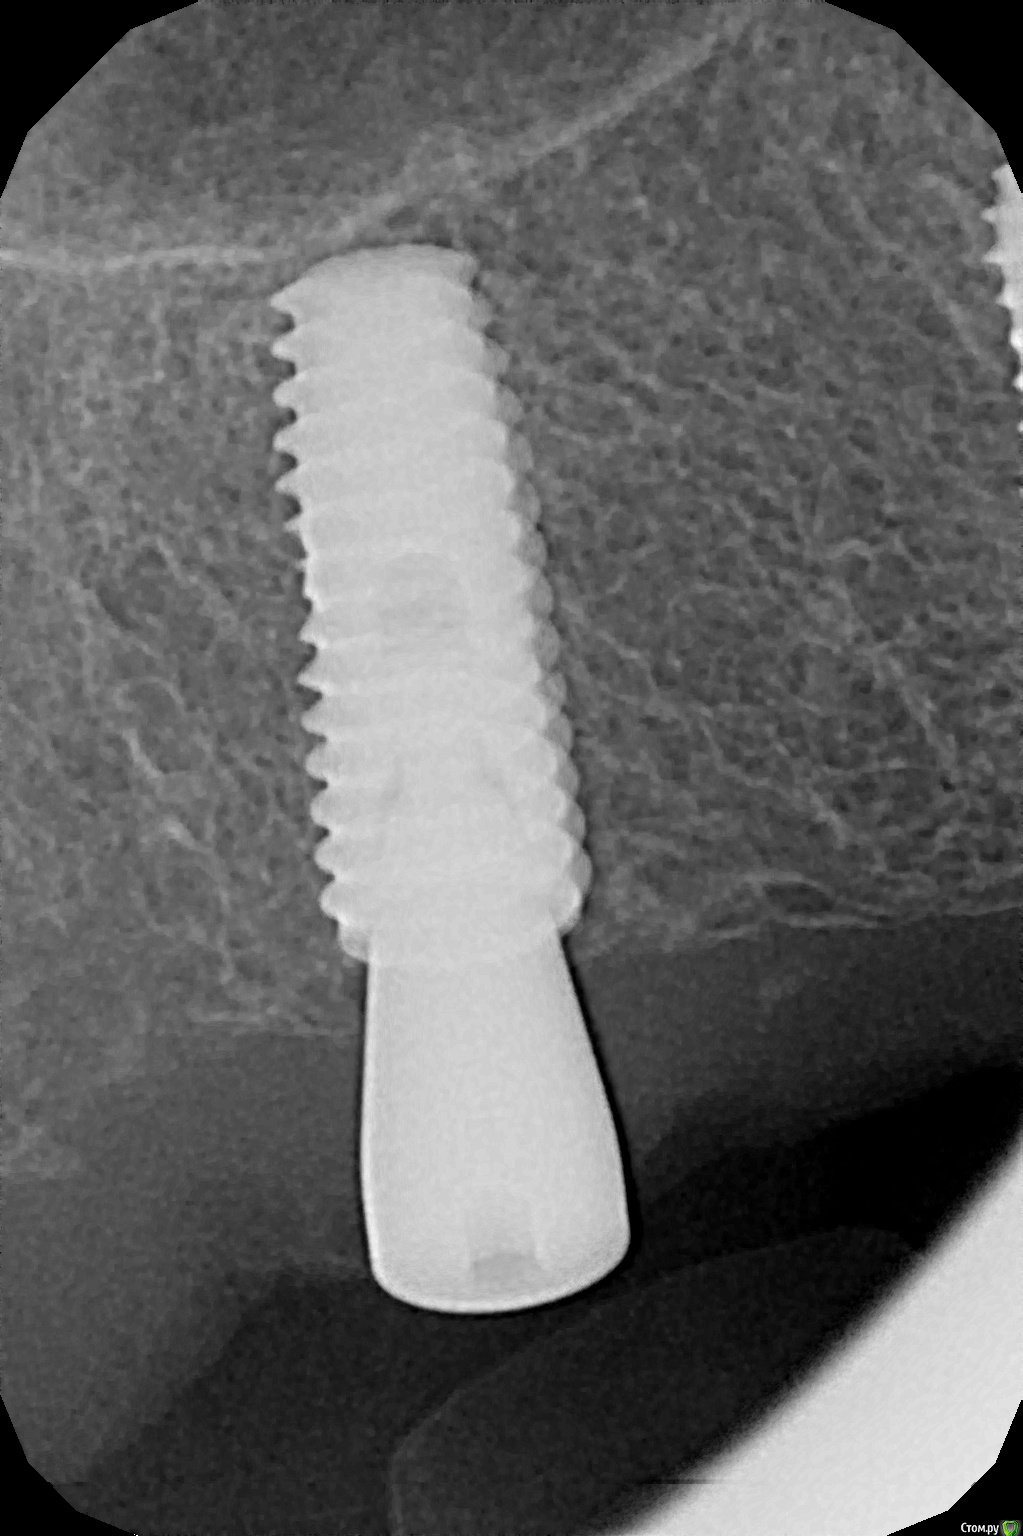

kamranchick Опубликовано 26 декабря, 2016 Автор Поделиться Опубликовано 26 декабря, 2016 По просьбе криокова.Убрал имплантат с области 17. кюретаж, ничего нет в лунке(мягких тканей итд) глубиномером все проверил, ни перфораций, ничего такого, при оказывании силы на лунку, она начинала складываться(кость)Напомню что лунку я подготовливал компресионным набором, установлен имплантат был 4.0 на 11.5ммРешил подготовить новое ложе в области 1.6.прошел пилотной фрезой 2.0 и начал сразу ставить имплантат 5.0 на 13 мм.торк - 10. или 8. решил сразу поставить формирователь. я хз блин как ложе готовить. и что надо для этого.Думаю надо было может бикортиально зафиксироваться. 1 Ссылка на комментарий

kriokov Опубликовано 26 декабря, 2016 Поделиться Опубликовано 26 декабря, 2016 торк - 10. или 8. решил сразу поставить формирователь. я хз блин как ложе готовить. и что надо для этого.Думаю надо было может бикортиально зафиксироваться. я бы фдм не решился, загушил бы. Про бикортикально-- думаю выход, чуть глубже бы пилотником и суперлайн встал бы в кортикальную дна синуса. Оно и так не плохо, при такой длине болта 1 Ссылка на комментарий

kamranchick Опубликовано 1 марта, 2017 Автор Поделиться Опубликовано 1 марта, 2017 я бы фдм не решился, загушил бы. Про бикортикально-- думаю выход, чуть глубже бы пилотником и суперлайн встал бы в кортикальную дна синуса. Оно и так не плохо, при такой длине болтапришел пациент спустя 2 месяца. пытался пальцем прокрутить имплантат, стабильно пока, значит выдерживает 12-14 ньютон я так понял)вопрос, можно ли на 2.4 зуб по стандарту затянуть абатмент на 30 ньютон, а этот на 20? Ссылка на комментарий